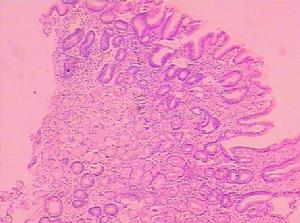

組織病理檢查:各種臨床類型的黃色瘤組織病理表現彼此相似真皮層內含有吞噬脂質的泡沫細胞(即黃色瘤細胞),有時可出現多核巨細胞(Touton細胞)病理早期有炎性細胞晚期有成纖維細胞增生現象。